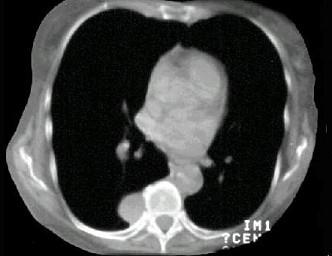

问题 男,67岁,无明显症状,胸片检查发现病变,进一步行CT检查如图,其最可能的诊断为 ( )

选项 A、后纵隔神经源性肿瘤 B、右侧胸膜间壁瘤 C、右下肺周围型肺癌 D、右下肺错构瘤 E、右下肺炎性假瘤

答案 A